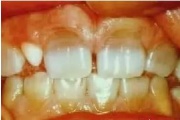

Normaalse jäävhammaskonna pilt küljelt ja eest vaadatuna.